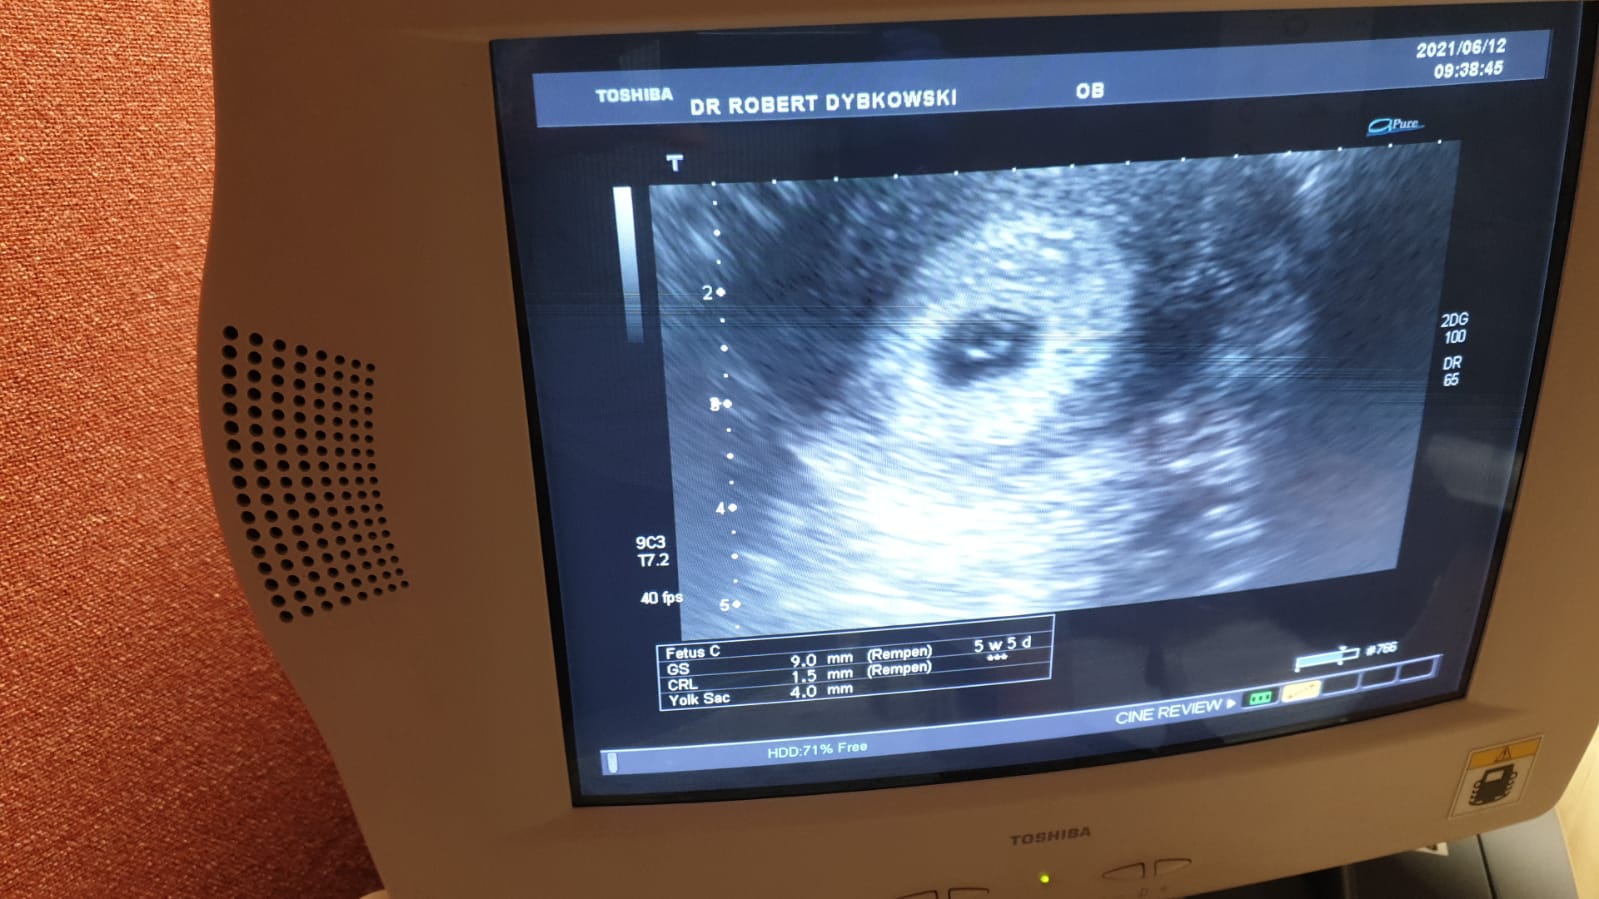

Bylam u ginekologa.Jestem w 5tygodniu i 5 dni wielkość płodu to 1.5 mm czy to nie za mało? Lekarz powiedział że za tydzień mam przyjść i powinno być bicie serca jeśli nie to znaczy że coś nie tak

IMG-20210612-WA0003.jpg

Oj moj błąd chodziło o 1.5mm.u mnie jest widoczny zarodek tylko niepokoi mnie wielkość.Lekarz powiedział że za tydzień czyli w 6 i 5 dni juz powinno być serce a jak nie będzie to znaczy że coś nie tak.Wydaje mi się że to bardzo szybko.